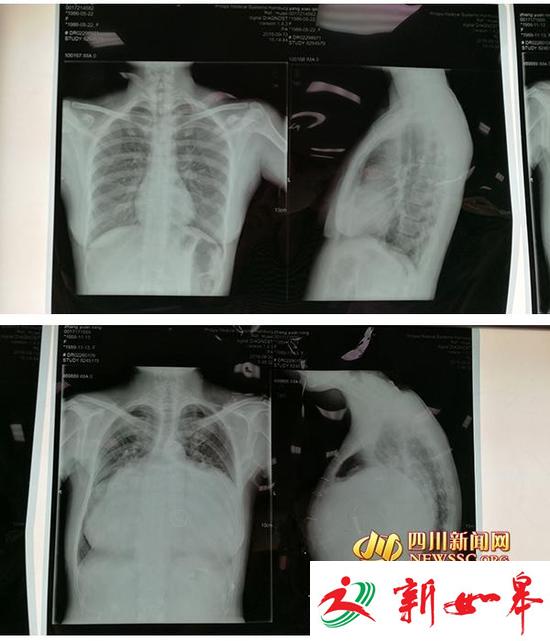

上图为正常人的胸部CT。下图为张女士的胸部CT,可以看到,她的心脏几乎占满左右胸腔。

方元教授告诉四川新闻网记者,张女士有一颗巨大心脏。“她的心脏是正常人的4-5倍,几乎占满了左右胸腔。”张女士的巨大心脏给心脏起搏器的安置带来了困难。安置心脏起搏器是一种不开胸腔,在X光透视下进行的微创介入手术。通俗的说,医生通过静脉血管,将心脏起搏器的电极导线植入心脏,再将电极导线和心脏起搏器相连接,最后,将心脏起搏器埋置在相应的皮下组织里。

而这种手术方式是方元教授在多次困难手术中不断积累经验,通过自己的摸索得来的,在国内属首创。据方元教授介绍,在之前,他也做过心脏大的患者的心脏起搏器安置手术,但像这次这么大的心脏还是第一次。一般来说,正常人的心胸比是小于0.5的,而张女士的心胸达到了0.95。目前,国内文献中尚未发现心胸比达到0.95的患者成功安置心脏起搏器的案例。